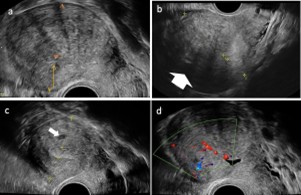

Adenomyosis disrupts the normal structure and function of the uterus. Specific phenotypes of adenomyosis include a bulky, globular uterus, asymmetrical myometrial thickening, myometrial cysts, irregular/interrupted junctional zone, hyperechoic islands, trans lesional vascularity and echogenic sub-endometrial lines and buds (21,29,30). The asymmetric or irregular thickening of the myometrium involves one wall (anterior, posterior, or lateral) appearing significantly thicker than the others. This asymmetrical thickening depicts areas with adenomyotic foci/infiltration. Myometrial cysts are circumscribed anechoic cystic areas seen within the myometrium, often corresponding to dilated adenomyotic glands (20,29). The junctional zone is a thin hypoechoic line that separates the endometrium from the outer myometrium (21). It appears thickened, interrupted, or ill-defined due to infiltration by adenomyotic lesions. Hyperechoic islands are regions of increased echogenicity in a linear or nodular pattern scattered within the myometrium (21). On Doppler imaging, trans lesional vascularity is seen as increased vascularity with prominent penetrating vessels running through the adenomyotic areas within the myometrium. Echogenic sub-endometrial lines and buds are fine echogenic linear bud-like projections and striations extending from the endometrium into the myometrial substance, highlighting infiltration by endometrial tissue into the myometrium (29) (Figure 2).

Figure 2: 2-D sonographic imaging of a non-gravid uterus in a longitudinal section highlighting typical phenotypes of adenomyosis. (a) See the globular shape with an asymmetrical myometrial wall-thickening (posterior thicker than anterior – orange arrows), the heterogeneous myometrium with hyperechoic regions, and hypoechoic striations. (b) asymmetrical myometrial wall-thickening (anterior thicker than posterior), the heterogeneous myometrium with fan-shaped shadowing (white arrow). Note the ill- indistinct endometrial-myometrial border (c) A solitary myometrial cyst on the posterior wall (white arrow). (d) Few diffuse vessels (increased vascularity) can be seen on colour Doppler